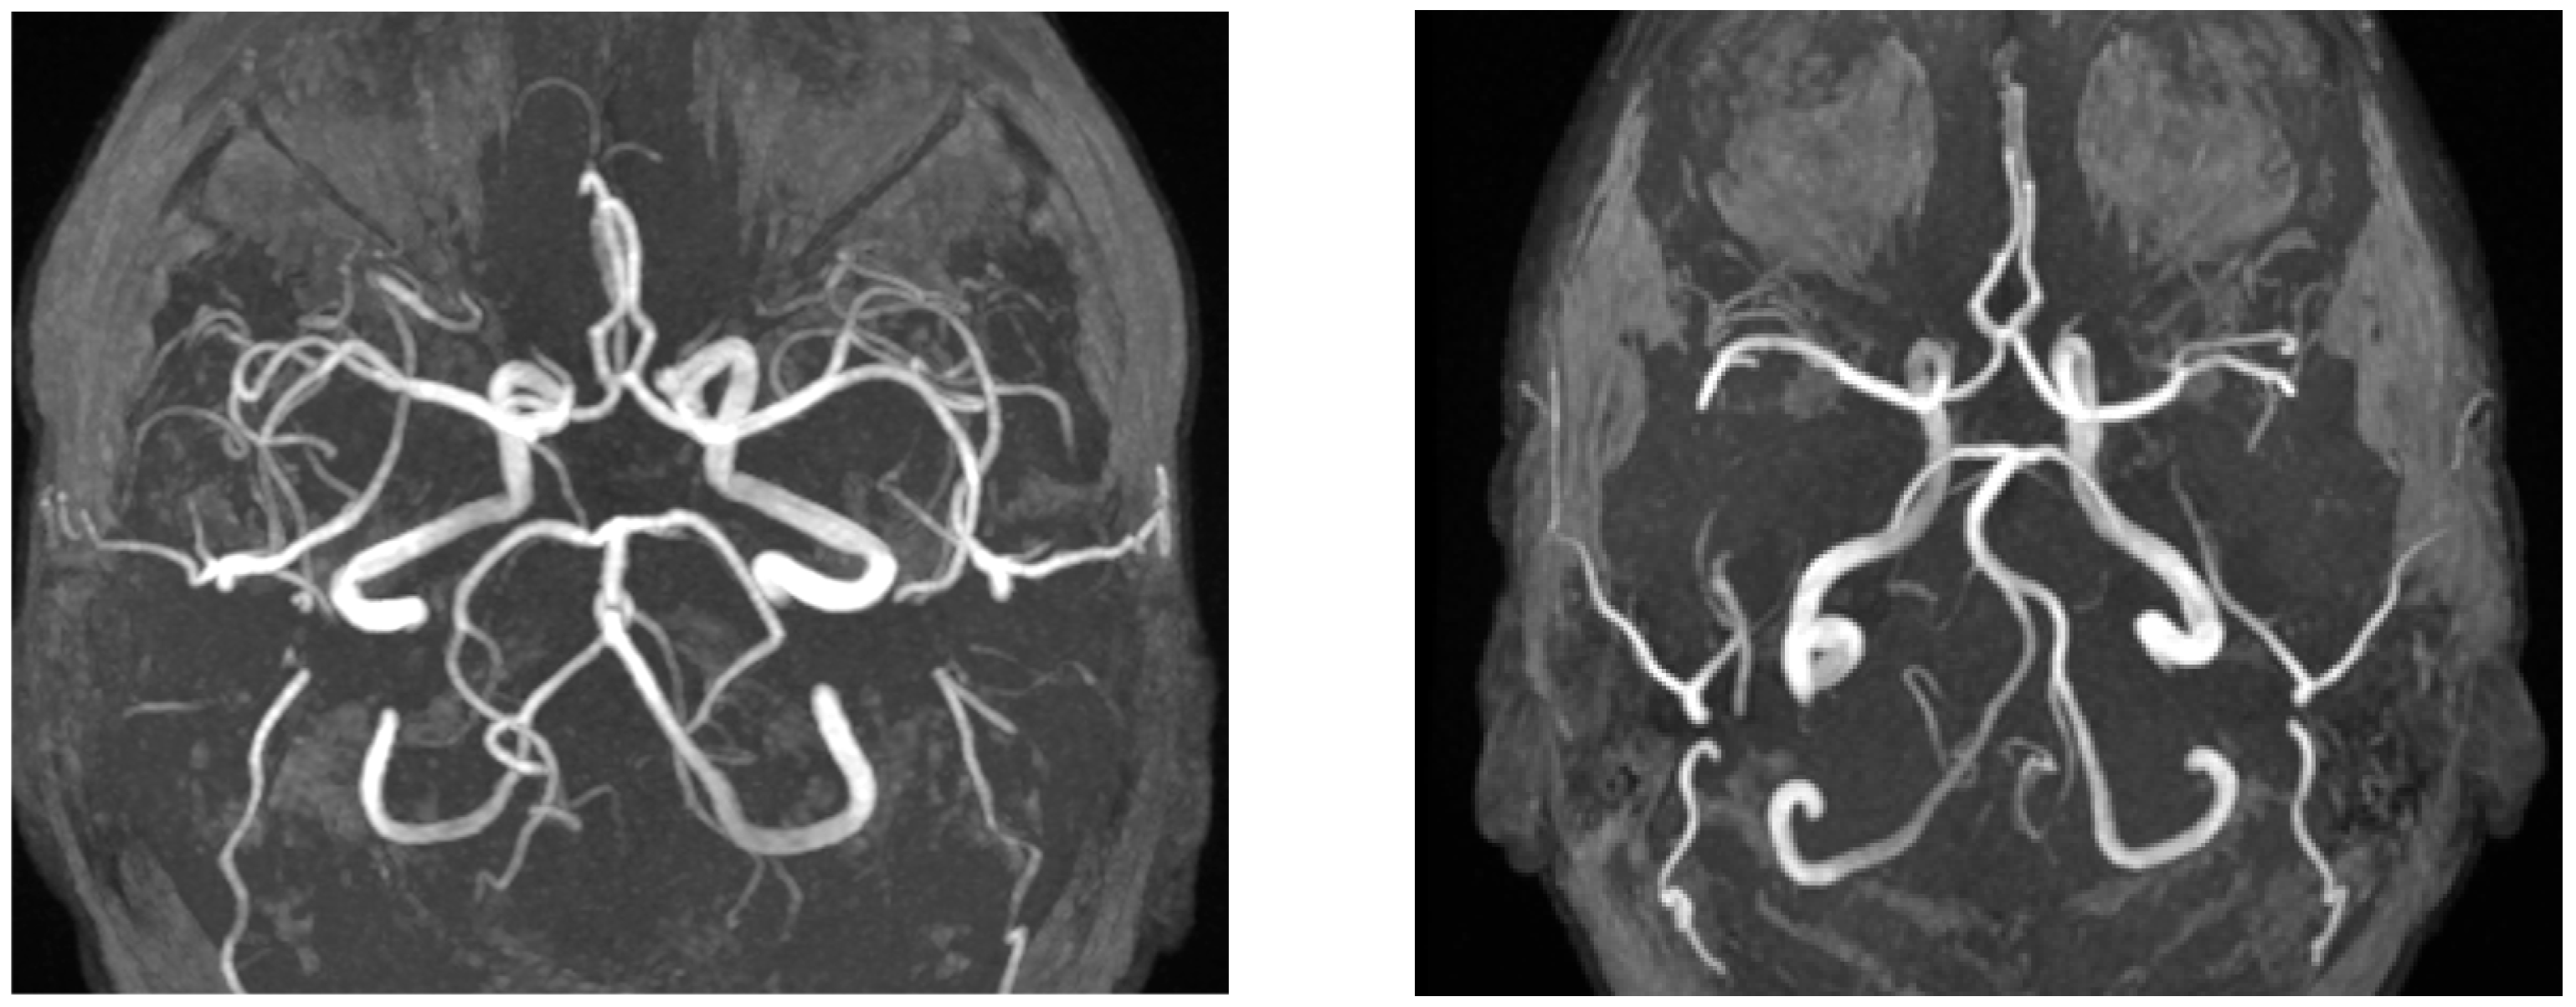

Significant differences were detected in white matter lesions (p = 0.001, see Figure 2), lacunar lesions (p = 0.047), Circle of Willis variation (p = 0.03), and sinusitis/sinus abnormalities (p = 0.005). Other MRI findings, including cortical atrophy, vascular lesion, and vascular encephalopathy, did not show statistically significant differences (p > 0.05).

Representative images of Circle of Willis variations are shown in Figure 4.

Figure 4. The left image (axial TOF-MRA) shows a variation of the basilar artery in a patient from the vertigo group, whereas the right image (axial TOF-MRA) demonstrates a control patient with a normal Circle of Willis.